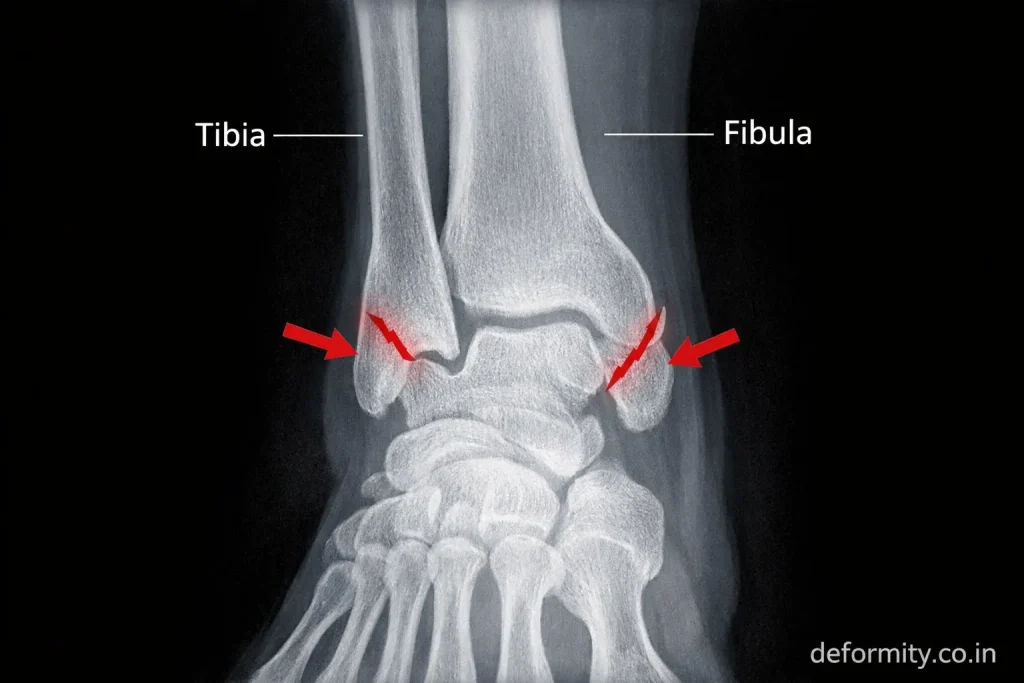

A bimalleolar ankle fracture is a serious injury in which both sides of the ankle joint break – the medial malleolus (inner ankle) and lateral malleolus (outer ankle). Because two stabilizing bones are fractured, the ankle joint becomes unstable and usually requires surgical fixation to restore proper alignment and prevent long-term complications such as arthritis, stiffness, or chronic instability.

A bimalleolar fracture refers to a break in both malleoli of the ankle:

- Medial malleolus (distal tibia)

- Lateral malleolus (distal fibula)

These two bones form the ankle mortise, which stabilizes the talus and allows smooth movement during walking. When both sides fracture, the ankle joint becomes unstable and cannot properly support body weight.

X-ray Imaging

X-rays confirm the diagnosis and show the fracture pattern.

Standard views:

- AP view

- Lateral view

- Mortise view

These help determine displacement and joint alignment.